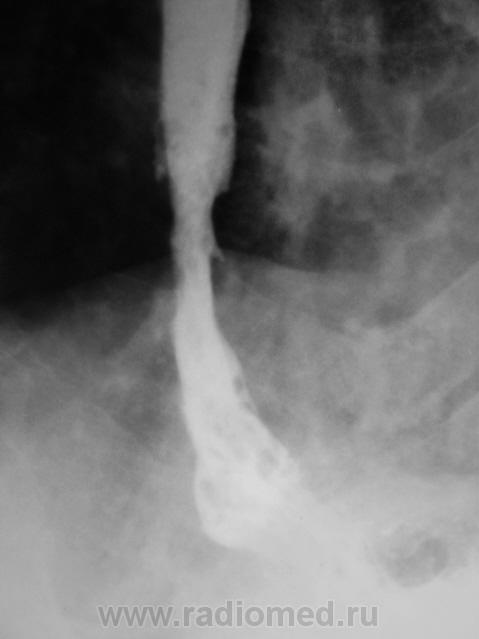

Пациент направлен на рентгенологическое исследование пищевода после ФГДС с диагнозом - "Пищевод Барретта".

Пациент первично был направлен в онкологический диспансер (областной). От туда он был направлен по месту жительства для производства ФГДС, которая и была проведена, был выставлен выше указанный диагноз.

После ФГДС, врач эндоскопист рекомендовал провести рентгеновское исследование пищевода.

1. Пищеводно-желудочный переход отсутствует - это одно из подтверждений пищевода Баррета.

2. Наблюдаемое сужение может быть следствием эзофагеального стеноза в зоне трансформации эпителия - это тоже подтверждение пищевода Баретта, но как без биопсии дифференцировать с инфильтративной формой рака....

3. Нишеподобное выпячивание по левой стенке может быть пептической язвой - это тоже характерно для пищевода Баретта....

4. Изменения в кардиальном отделе желудка по медиальной стенке - интересное и непонятное явление...думаю без биопсии тут никто не разберется, это и отек слизистой, это и рост в просвет...

Циркулярное сужение в н/3 + отсутствие складок на уровне поражения + формирующееся престенотическое расширение = рак н/3 пищевода. Ну, а Барреты? А Барреты потом...